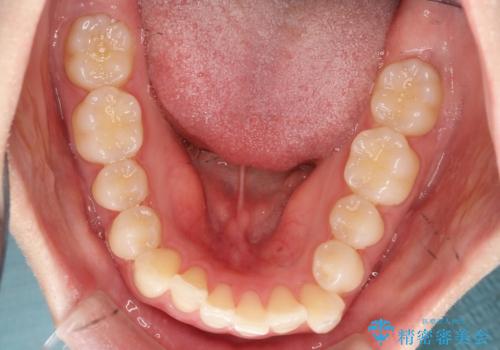

- 左上2の反対咬合(交叉咬合)をインビザラインを用いて治療しました。反対咬合は、歯列の不正咬合の一つであり、上の歯が下の歯よりも内側に位置する状態です。反対咬合は咀嚼や発音に影響を与えることがあります。

左上2の反対咬合をインビザラインで治療する際に、IPR(Interproximal Reduction)を行いました。 IPRとは、隣接する歯の間のエナメル質をわずかに削る手法で、歯の幅を減少させることによって歯列を整える技術です。